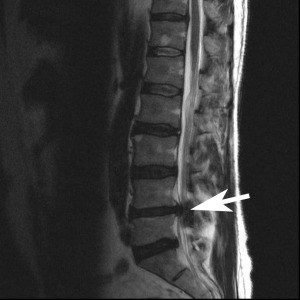

Below are two images, which one looks more painful?

These two images are both “bad” for the patient, but you cannot tell the extensive injuries by simply looking at an image. There is no pain visible in either of them. Letter A is a significant herniation, pressing directly on the spinal canal, and impeding on the spinal cord itself. Letter B, has a piece of vertebral disc that has broken off within the spinal canal (known as a sequestration) and has migrated upwards.

With reference to images A and B above. Image A has cauda equina syndrome, known as complete loss of function of the muscles and structures of the “saddle” area of the pelvis. While Image B is paraplegic from the legs down, without any “saddle” disruption. Both of these cases are no longer considered “conservative” with terms of treating, they are immediate surgical candidates. Disc injuries range from non-painful, to extremely painful, to absolute medical emergencies.